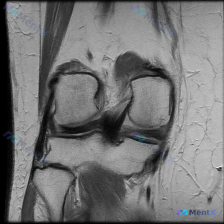

这是一张膝关节MRI冠状位T1加权成像(T1WI),用户提示观察内容为「软骨异常」。

- 骨骼结构:股骨远端、胫骨近端显示清晰,骨皮质低信号、骨髓腔中等信号均匀,没有明显骨髓信号异常

- 半月板:内外侧半月板都是典型低信号三角形,形态规整,连续性好,没有高信号线穿透关节面,排除明确撕裂

- 韧带结构:髁间窝可见部分前交叉韧带,信号正常、连续;内外侧副韧带都保持连续,信号形态无异常

- 关节对线与骨表面:股骨胫骨对线基本对齐,没有内翻外翻畸形;关节软骨下骨皮质轮廓光整,没有骨赘、侵蚀破坏或骨软骨缺损

- 其他:关节腔内没有明显积液,周围软组织层次清晰,没有水肿或肿块

整体来看,当前这张单层面T1WI影像上没有发现明确的结构性损伤或病理改变,也没有看到明确的软骨异常。